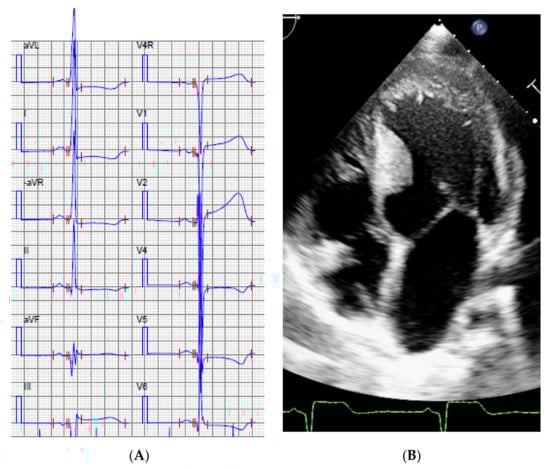

| 2. | I:1 | 22 | M | 1 | Apical LVH | 2 | 8 | Mother SCD due to HCM | No result | No result |

| 3. | II:1 | 14 | M | 0 | First symptom pro-longed QTc, rapid evolving to HCM ASH and LVNC. | 2 | 3 | Mother mVSD, LVNC | ABCC9 Chr12(GRCh37):g.21997457A>C, NM_005691.3:c.3275T>G p.I1092S | PP3 VUS/Yes |